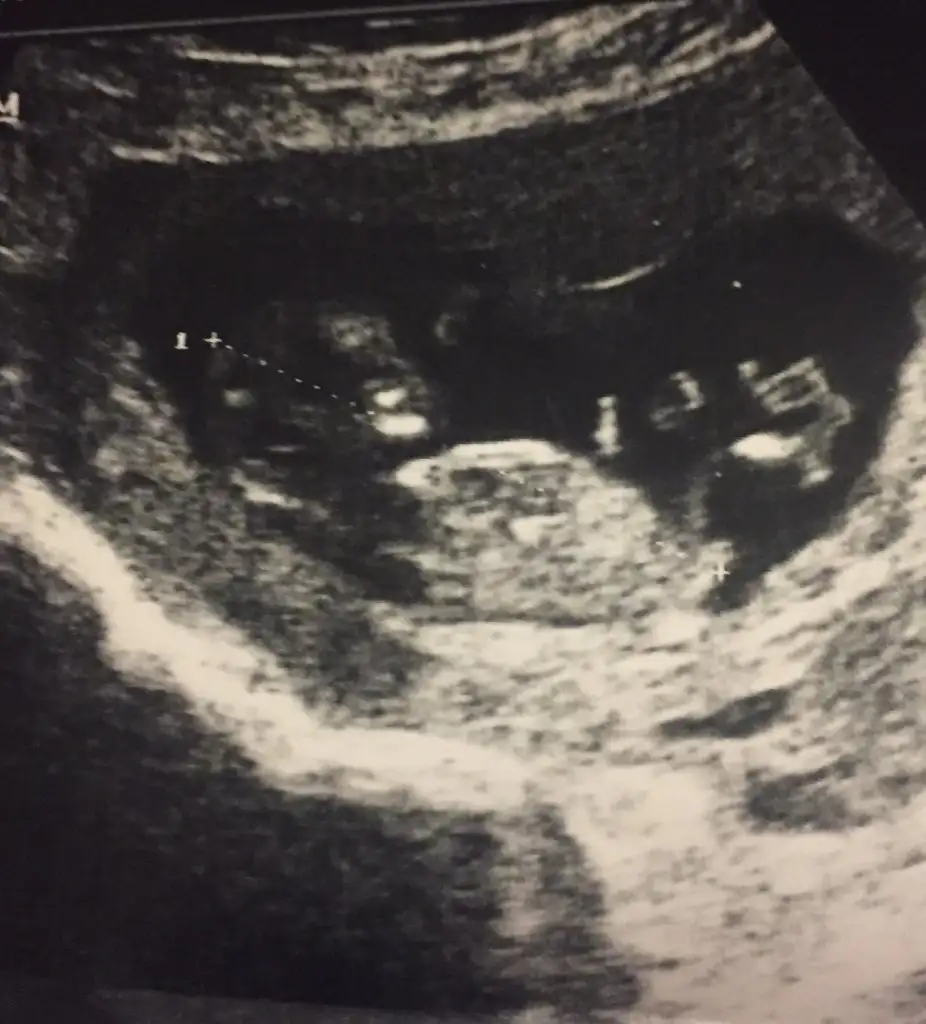

Çift yumurta ikizi mi bunlar? Görüntüler hiç net değil maalesef.ama ben sağdaki usg yi erkeğe.soldakini de kıza benzettim kafa yapılarını.yada ikiside erkek olabilir ,evet evet ikiside erkek diyorumbunlarda benim bebişlerimin 12haftalık görüntüleri.Daha önce 10haftalık koymuştum.çok net değildi

evet çift yumurta ikizi canımÇift yumurta ikizi mi bunlar? Görüntüler hiç net değil maalesef.ama ben sağdaki usg yi erkeğe.soldakini de kıza benzettim kafa yapılarını.yada ikiside erkek olabilir ,evet evet ikiside erkek diyorum![]()

Doktor bir tahminde bulundu mu peki?hele Soldaki usg den çok emin olamadım.görüntüler hiç net değil çünkü.doktor ne dedi?evet çift yumurta ikizi canım

sordum ama daha erken dediDoktor bir tahminde bulundu mu peki?hele Soldaki usg den çok emin olamadım.görüntüler hiç net değil çünkü.doktor ne dedi?

Biri kız biri erkeksordum ama daha erken dedibi de şimdi bunları ,çektim videodan belki yardımcı olur

Canım soldaki kız sağdaki erkek.foto da soldakinden emin olamamıştım videoda daha net.nub çizgisi göremiyorum.kafa yapılarına göre yorum yaptım.sonucu öğrenince yazarsınsordum ama daha erken dedibi de şimdi bunları ,çektim videodan belki yardımcı olur

teşekkürler canım.öğrenince yazacağımCanım soldaki kız sağdaki erkek.foto da soldakinden emin olamamıştım videoda daha net.nub çizgisi göremiyorum.kafa yapılarına göre yorum yaptım.sonucu öğrenince yazarsın

Sol erkek sağ kızsordum ama daha erken dedibi de şimdi bunları ,çektim videodan belki yardımcı olur